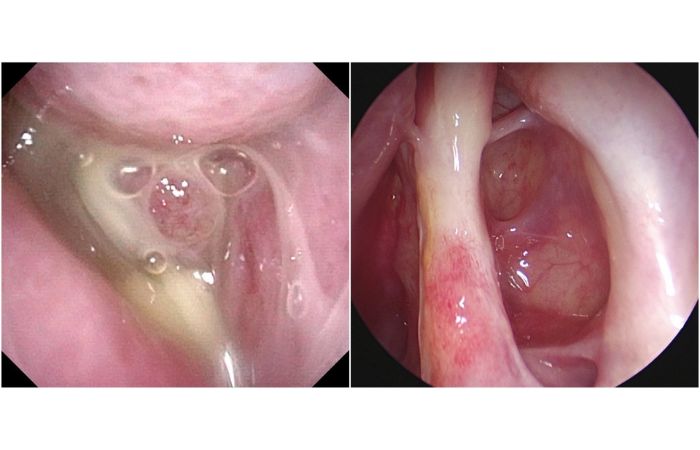

鼻竇炎初期能以一般感冒藥治療,但是如果變成慢性鼻竇炎,出現嚴重併發症,就需要手術治療。不同於傳統手術必須將鼻竇整個切除,「功能性內視鏡鼻竇炎手術」是透過鼻孔的自然孔洞將內視鏡伸入病灶,把腫脹的息肉切除,擴大鼻竇開口並清除發炎黏液。